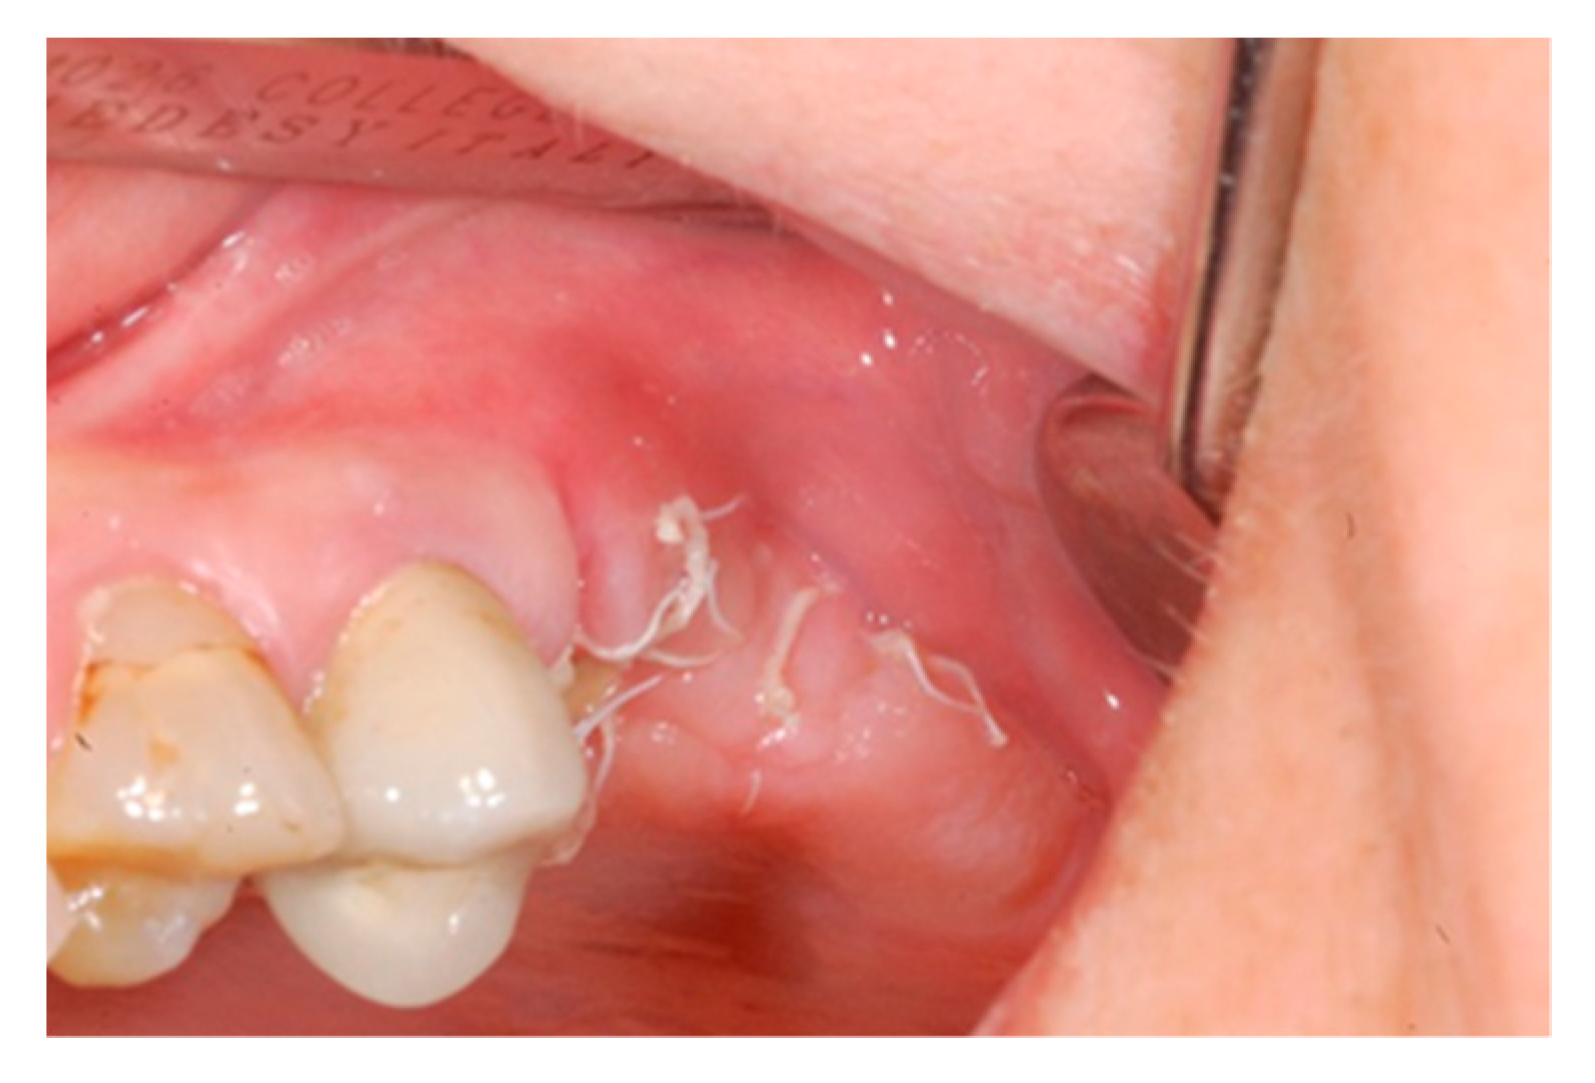

2. Case Report

3. Results